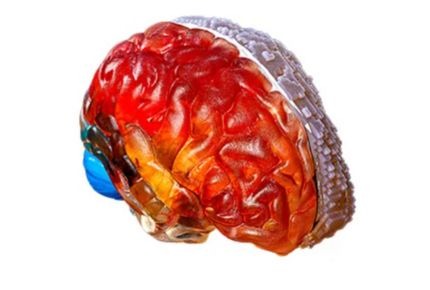

Alakítsa a sebészet jövőjét páciens-specifikus 3D modellekkel. Javítsa az előkészítést, finomítsa a műtéti technikákat, és optimalizálja az eszközöket a jobb eredmények érdekében. Az anatómiailag pontos modellek javítják a kommunikációt és rövidítik a műtéti időt.

Szerezzen gyakorlati tapasztalatot élethű modellekkel, amelyek lehetővé teszik műtéti technikák gyakorlását realista szimulációk során. Növelje a magabiztosságot összetett beavatkozásoknál, és vizsgálja a biomechanikát és patológiákat pontos másolatokkal.

Legnépszerűbb 3D nyomtató az anatómiai modellezéshez; a legszélesebb anyagválasztékkal a komplex, élethű modellekhez. Ideális minden orvosi feladatra.

Ideális sebészeti felkészüléshez, a pácienskimenetek javításához és a termékfejlesztési innováció felgyorsításához. Élethű anatómiai modellek magas biomechanikai pontossággal.